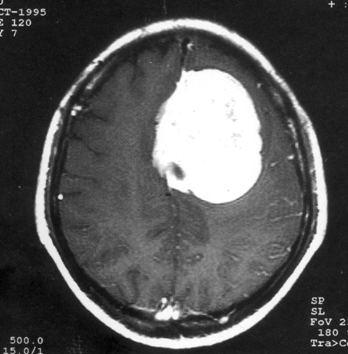

问题 病历摘要:??患者女性,37岁。大便时突起炸裂样头痛3小时,伴喷射样呕吐。既往体健。体检:T37.5℃,BP145/90mmHg,R20次/分,P85次/分。神志清楚,颅神经检查无异常,颈强直,克、布氏征(-),四肢肌力、肌张力正常,病理征(-)。 动脉瘤术中出血时,可采取哪些措施?提示:入院后第?2日患者行右翼点开颅瘤颈夹闭术,术中分离瘤颈时,动脉瘤破裂。